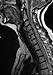

The definitive guide to internal medicine is more essential than ever with the latest in disease mechanisms, updated clinical trial results and recommended guidelines, state of the art radiographic images, therapeutic approaches and specific treatments, hundreds of demonstrative full color drawings, and practical clinical decision trees and algorithms